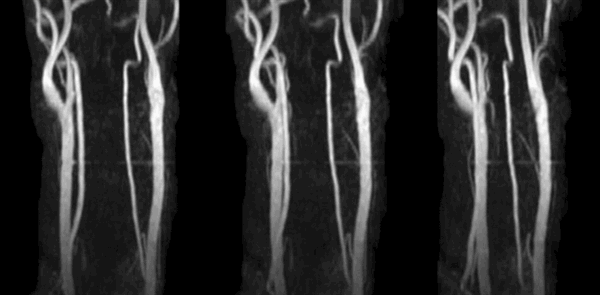

КТ снимки сосудов шеи

КТ-ангиография сосудов шеи с контрастом - золотой стандарт диагностики, но чтобы получить максимальную пользу от исследования, необходима слаженная работа профессионалов. Расшифровкой результатов занимается рентгенолог. В центре “Магнит” в Санкт-Петербурге КТА - одна из востребованных процедур, а наши врачи ответят на любые вопросы. В сложных случаях оценка томограмм проводится коллегиально. Представляем Вашему вниманию несколько томограмм, где четко видны патологические изменения:

КТ-ангиограмма кровеносных сосудов в области шеи. Позвоночная артерия находится между вертикальными линиями. Стрелка указывает на позвоночник

Коронарное изображение МСКТ демонстрирует саккулярный затек контраста (толстая стрелка) из правой внутренней сонной артерии (псевдоаневризма). Левая сонная артерия (тонкая стрелка) не повреждена.